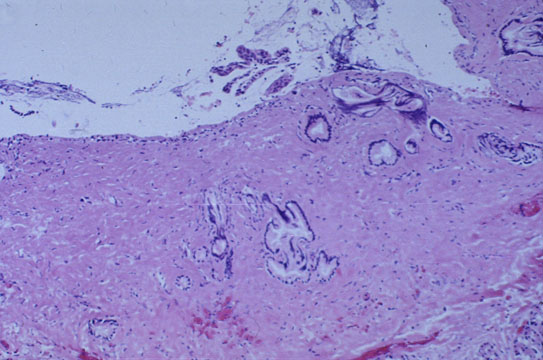

Фотографии медицинских исследований инсулиномы и синдрома Триады Уиппла